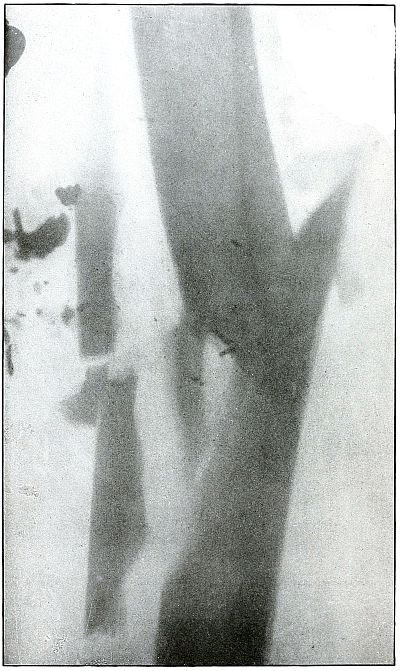

Gunshot fracture, tibia and fibula |

130 |

| 61. |

Gunshot fracture, tibia and fibula |

132 |